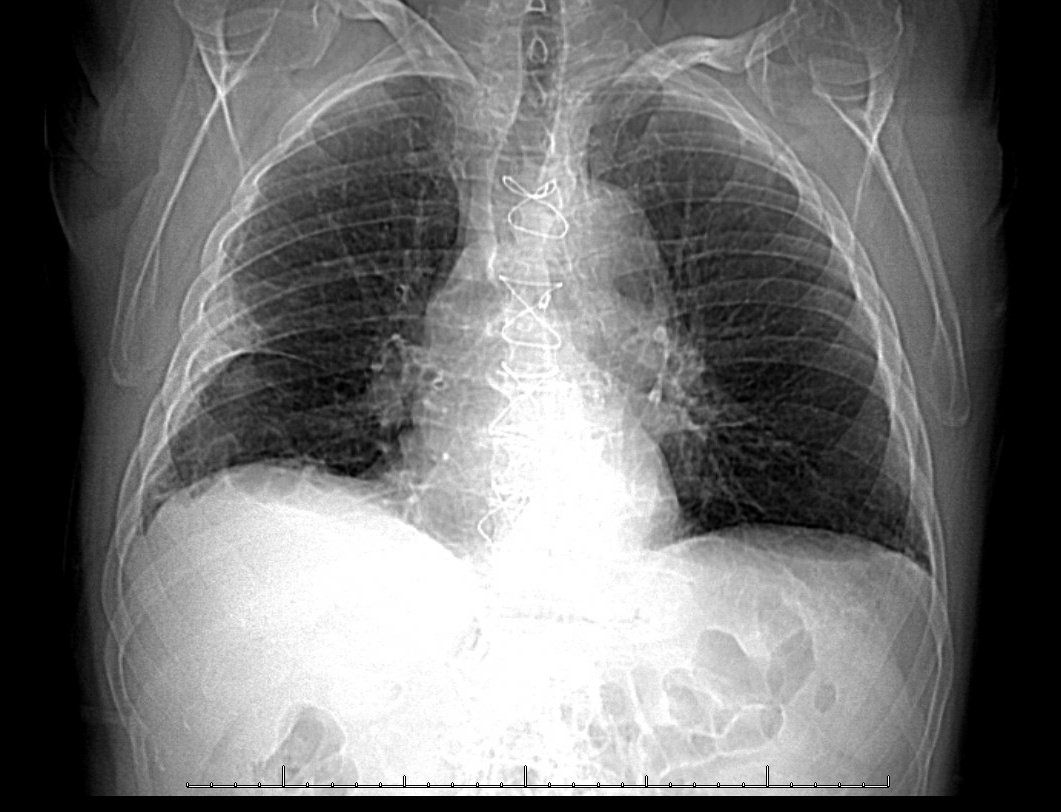

Varón de 75 años con pinchazos en tórax desde hace 3 días que aumentan al inspirar, sin fiebre, taquicardia ni taquipnea. Recibió bypass en DA hace 8 años y tiene artrosis de cadera muy dolorosa por la que lleva 4 meses encamado, en espera para prótesis 🥴⏳ Image

El diagnóstico diferencial inicial fue amplio. No obstante, se realizó una Rx de tórax (en tweet previo) con un hallazgo característico que orientó rápidamente el diagnóstico ¿Sabrías decirnos cuál es? 🤔💭

Exacto! 🌟 La imagen es una joroba de Hampton 🐪 Es un hallazgo radiológico clásico en estos casos; una opacidad triangular con vértice hacia el hilio pulmonar y "joroba" curva. Es rara pero característica de un infarto pulmonar tras un TEP. Image